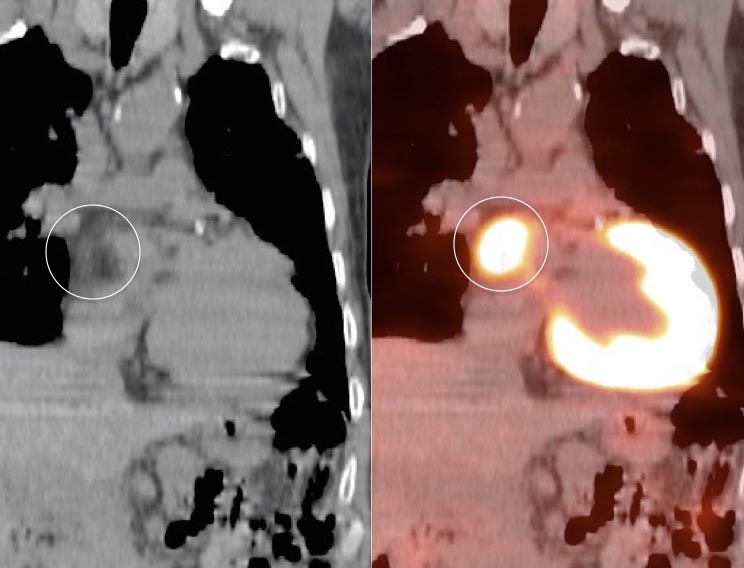

Lipomatous Hypertrophy of the Inter-Atrial Septum

LHIAS is focal fatty infiltration of the inter-atrial septum of the heart. It behaves as hypermetabolic brown fat, and is often intensely FDG-avid, appearing mass-like on the PET images.

Although a non-malignant finding, there are reports of a rare association with arrhythmias.

Diagnosis of this hypermetabolic PET finding is confirmed by the presence of only fat on the co-registered CT images.

Misdiagnosis of this “Aunt Minnie” is unacceptable (as in the terrified patient referred to us from Europe, who flew in with his images to further evaluate his “heart cancer”).

Although benign, we recommend mentioning this finding in the body of the report, as it often looks impressive on the PET images and can prompt a call from a clinician concerned that you “missed” a mass.

We generally report:

“Incidentally noted is lipomatous hypertrophy of the inter-atrial septum, typically of no clinical significance.”